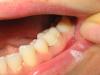

DOK Elena Опубликовано 26 июня, 2008 Поделиться Опубликовано 26 июня, 2008 (изменено) Пациентка была направлена мной к ортопеду после окончания ортодонтического лечения. ортодонту не удалось довести 36 до контакта с 26 по 1 классу ( в результате 36 завален язычно ). 36 имел ранее поставленную пломбу 1 класс без претензий к качеству и рецидива. приняли решение изготовить вкладку из оксида циркония в 36 для восстановления контакта с 26. с точки зрения ортодонта изготовленная вкладка воссоздает контакт с антогонистом идеально, бугры там тоже отличные. Но есть одно сомнение : соответствует ли это все эстетике и что в таких случаях вообще считается допустимым по красоте. пациентка недовольна. пломба, по ее мнению, была красивее. На приложенных фото вкладка фиксирована на временном цементе. что думаете, переделывать? техник говорит, что лучше не сделает.... ( имеется ввиду вестибулярная поверхность вкладка-зуб ). Может какую-то другую конструкцию делать? И можно ли вообще в таких случаях сделать переход от вкладки к эмали зуба незаметным? Изменено 26 июня, 2008 пользователем DOK Elena Ссылка на комментарий

Fred Опубликовано 26 июня, 2008 Поделиться Опубликовано 26 июня, 2008 Пациентка была направлена мной к ортопеду после окончания ортодонтического лечения. ортодонту не удалось довести 36 до контакта с 26 по 1 классу ( в результате 36 завален язычно ). 36 имел ранее поставленную пломбу 1 класс без претензий к качеству и рецидива. приняли решение изготовить вкладку из оксида циркония в 36 для восстановления контакта с 26. с точки зрения ортодонта изготовленная вкладка воссоздает контакт с антогонистом идеально, бугры там тоже отличные. Но есть одно сомнение : соответствует ли это все эстетике и что в таких случаях вообще считается допустимым по красоте. пациентка недовольна. пломба, по ее мнению, была красивее. На приложенных фото вкладка фиксирована на временном цементе. что думаете, переделывать? техник говорит, что лучше не сделает.... ( имеется ввиду вестибулярная поверхность вкладка-зуб ). Может какую-то другую конструкцию делать? И можно ли вообще в таких случаях сделать переход от вкладки к эмали зуба незаметным? Вкладкой, наврядли, получится сделать незаметный переход ... Особенно, из диоксида циркония, у которого не только оптические свойства очень сильно отличаются от оптических свойств зуба, но и с адгезией проблемы. Ссылка на комментарий

Каплан Опубликовано 27 июня, 2008 Поделиться Опубликовано 27 июня, 2008 А сделать такую вкладку из керамики? Почему не рассматривается етот вариант? Хотя конечно коронку нормальную туда будет самое то, потому что свой зубик явно выделяется по цвету. ИМХО. Ссылка на комментарий

DOK Elena Опубликовано 27 июня, 2008 Автор Поделиться Опубликовано 27 июня, 2008 А сделать такую вкладку из керамики? Почему не рассматривается етот вариант? Хотя конечно коронку нормальную туда будет самое то, потому что свой зубик явно выделяется по цвету. ИМХО.принимая решение поставить вкладку из оксида циркония, руководствовалась механическими свойствами последнего,в его преимуществе к металлокерамике в плане прочности.сложности с эстетикой не приняла во внимание.хоту понять,то что я сейчас у пациента имею- MAX, или стоит настаивать на переделке. просто ранее с такими работами не сталкивалась.... Ссылка на комментарий

Гость Vini Vidi Vici Опубликовано 27 июня, 2008 Поделиться Опубликовано 27 июня, 2008 А нельзя чуть по-другому отпрепарировать вестибулярную поверхность и отправить-таки на переделку?Ещё с цветом немного не попали в линии перехода. Ссылка на комментарий